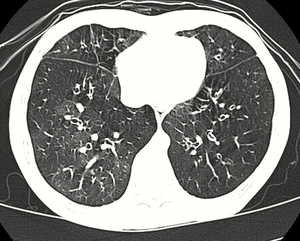

High resolution CT scan showing bronchiolitis obliterans with ground glass opacification, air trapping, and bronchial thickening[3] | |

Several tests are often needed to correctly diagnose bronchiolitis obliterans, including chest x-rays, diffusing capacity of the lung tests (DLCO), spirometry, lung volume tests, high-resolution CT (HRCT), and lung biopsy. Diffusing capacity of the lung (DLCO) tests are usually normal; people with early-stage BO are more likely to have normal DLCO. Spirometry tests usually show fixed airway obstructions and sometimes restriction, where the lungs can't expand fully. Lung volume tests may show hyperinflation (excessive air in lungs caused by air trapping). HRCT can also show air trapping when the person being scanned breathes out completely; it can also show thickening in the airway and haziness in the lungs. Transthoracic lung biopsies are preferable for diagnosis of constrictive BO compared to transbronchial biopsies; regardless of the type of biopsy, a diagnosis may only be achieved by examination of multiple samples.[20]